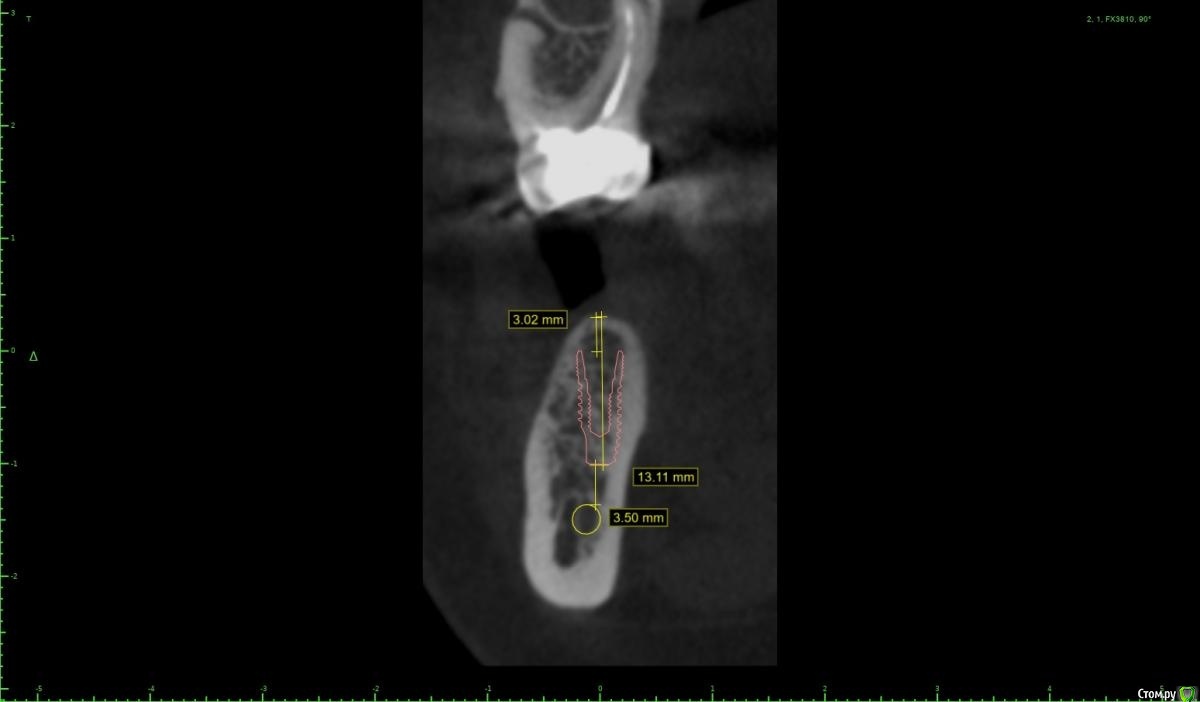

колесников Опубликовано 28 ноября, 2020 Поделиться Опубликовано 28 ноября, 2020 (изменено) Имплант 13 мм? Зачем? При планировании видно, что он упирается апексом в кортикалку. По этому и поставить не могли сразу. Торк 45. Если имплант плотно контактирует с компактной пластинкой,она резорбируется окончато,со всеми вытекающими. Стоило выбрать имплант 8.5мм. Если притопили имплант,зачем поставили заглушку? Имплант зарастёт придётся выпиливать ,откапывать заглушку,ломать то что наросло непосильным трудом. Хороший торк-ставьте рабочий фдм. Сомнения-мелкий фдм или заглушка +1. Рекомендую сделать контрольный кт и поставить фдм Изменено 28 ноября, 2020 пользователем колесников 5 Ссылка на комментарий

Женька Опубликовано 14 декабря, 2020 Автор Поделиться Опубликовано 14 декабря, 2020 (изменено) Наконец-то получил КТ от пациентки...Боли значительно уменьшились, практически не беспокоит... Коллеги, что думаете? Я так понимаю это уже не фон от титана? и вердикт всё-таки один? Сам склоняюсь всё-таки более к понаблюдать. Вестибулярно конечно очень тонко Толщина была ~ 6.7мм Изменено 14 декабря, 2020 пользователем Женька Ссылка на комментарий

Irouil Опубликовано 14 декабря, 2020 Поделиться Опубликовано 14 декабря, 2020 Ну и где тут язычно передавленная кортикалка? Меня смущает только картина в области верхушки симптомного винта, ну и заглубление Я бы дождался уже срока интеграции Ссылка на комментарий

Женька Опубликовано 14 декабря, 2020 Автор Поделиться Опубликовано 14 декабря, 2020 Ну и где тут язычно передавленная кортикалка? Меня смущает только картина в области верхушки симптомного винта, ну и заглублениеНе знаю, я про язычную кортику не говорил. Меня тоже смущает... и в области соседа такого фона (а это не фон я уверен) нет... А с заглублением что не так? по прицелам там 1.5-2мм, на кт почему-то этих мм вообще нет и как будто крестально стоят Ссылка на комментарий